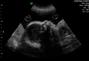

جنينك في الشهر السابع

يحمل الشهر السابع الكثير من التطور والنمو لدى الجنين ومنها:نمو الطفل يزداد حجم الرحم ( يبلغ ارتفاع الرحم بين ال24 و 28سم)تنفس الطّفل يصبح أكثر انتظاما.اكتمال أعضاء الطفل بشكل طبيعي .تأخذ الأذن مكانها النّهائي.لم يعد للطّفل مكان كافٍ في الرّحم وأصبحت حركاته أطول . يبلغ طول الطفل 42 سم ووزنه 1,5 ج.زوال الزغب والشعر من الوجه.تحسن السمع،بحيث بإمكانه سماع الأصوات الخارجية،لذلك يرتاح الجنين بعد ولادته لدى ضمه إلى صدر أمه بالقرب من قلبها.التمطط والتحرك بنشاط.